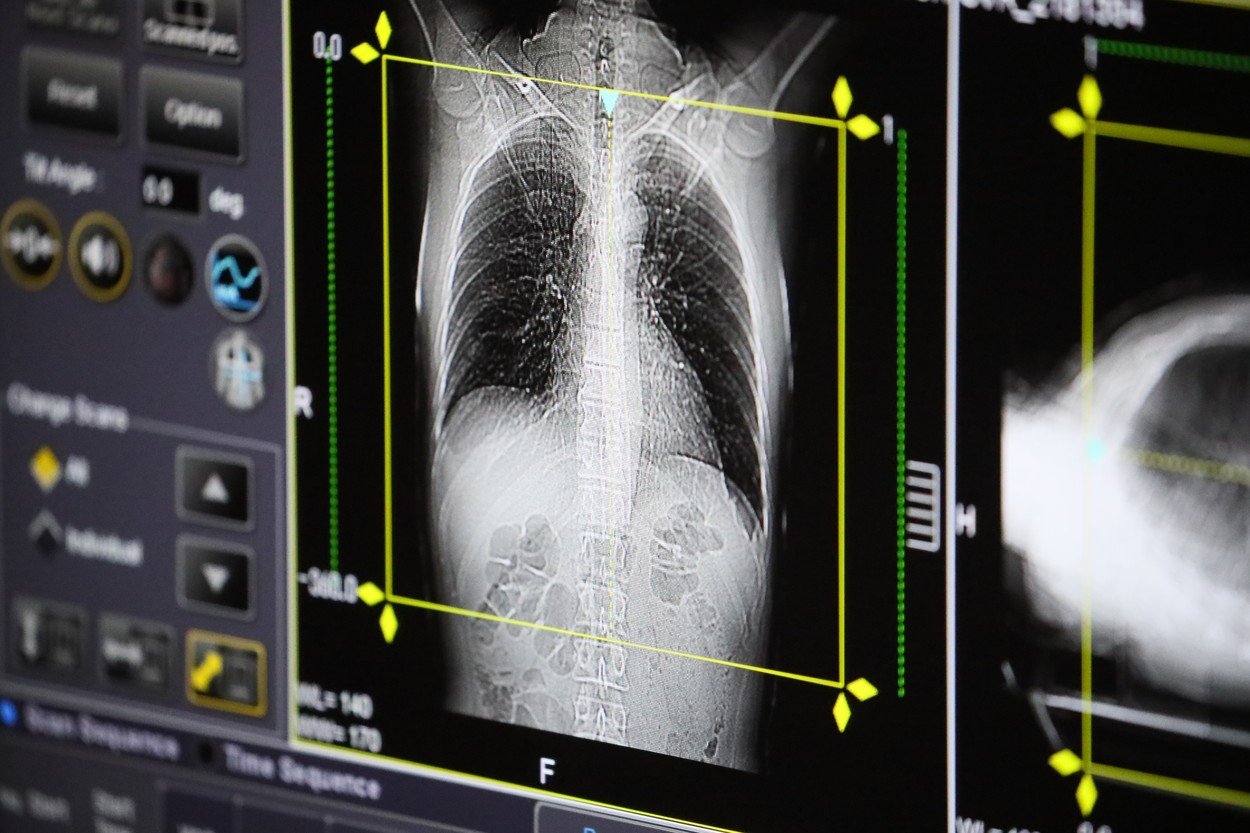

Tomografie pulmonarăFoto: Vladimir Gerdo / TASS / Profimedia